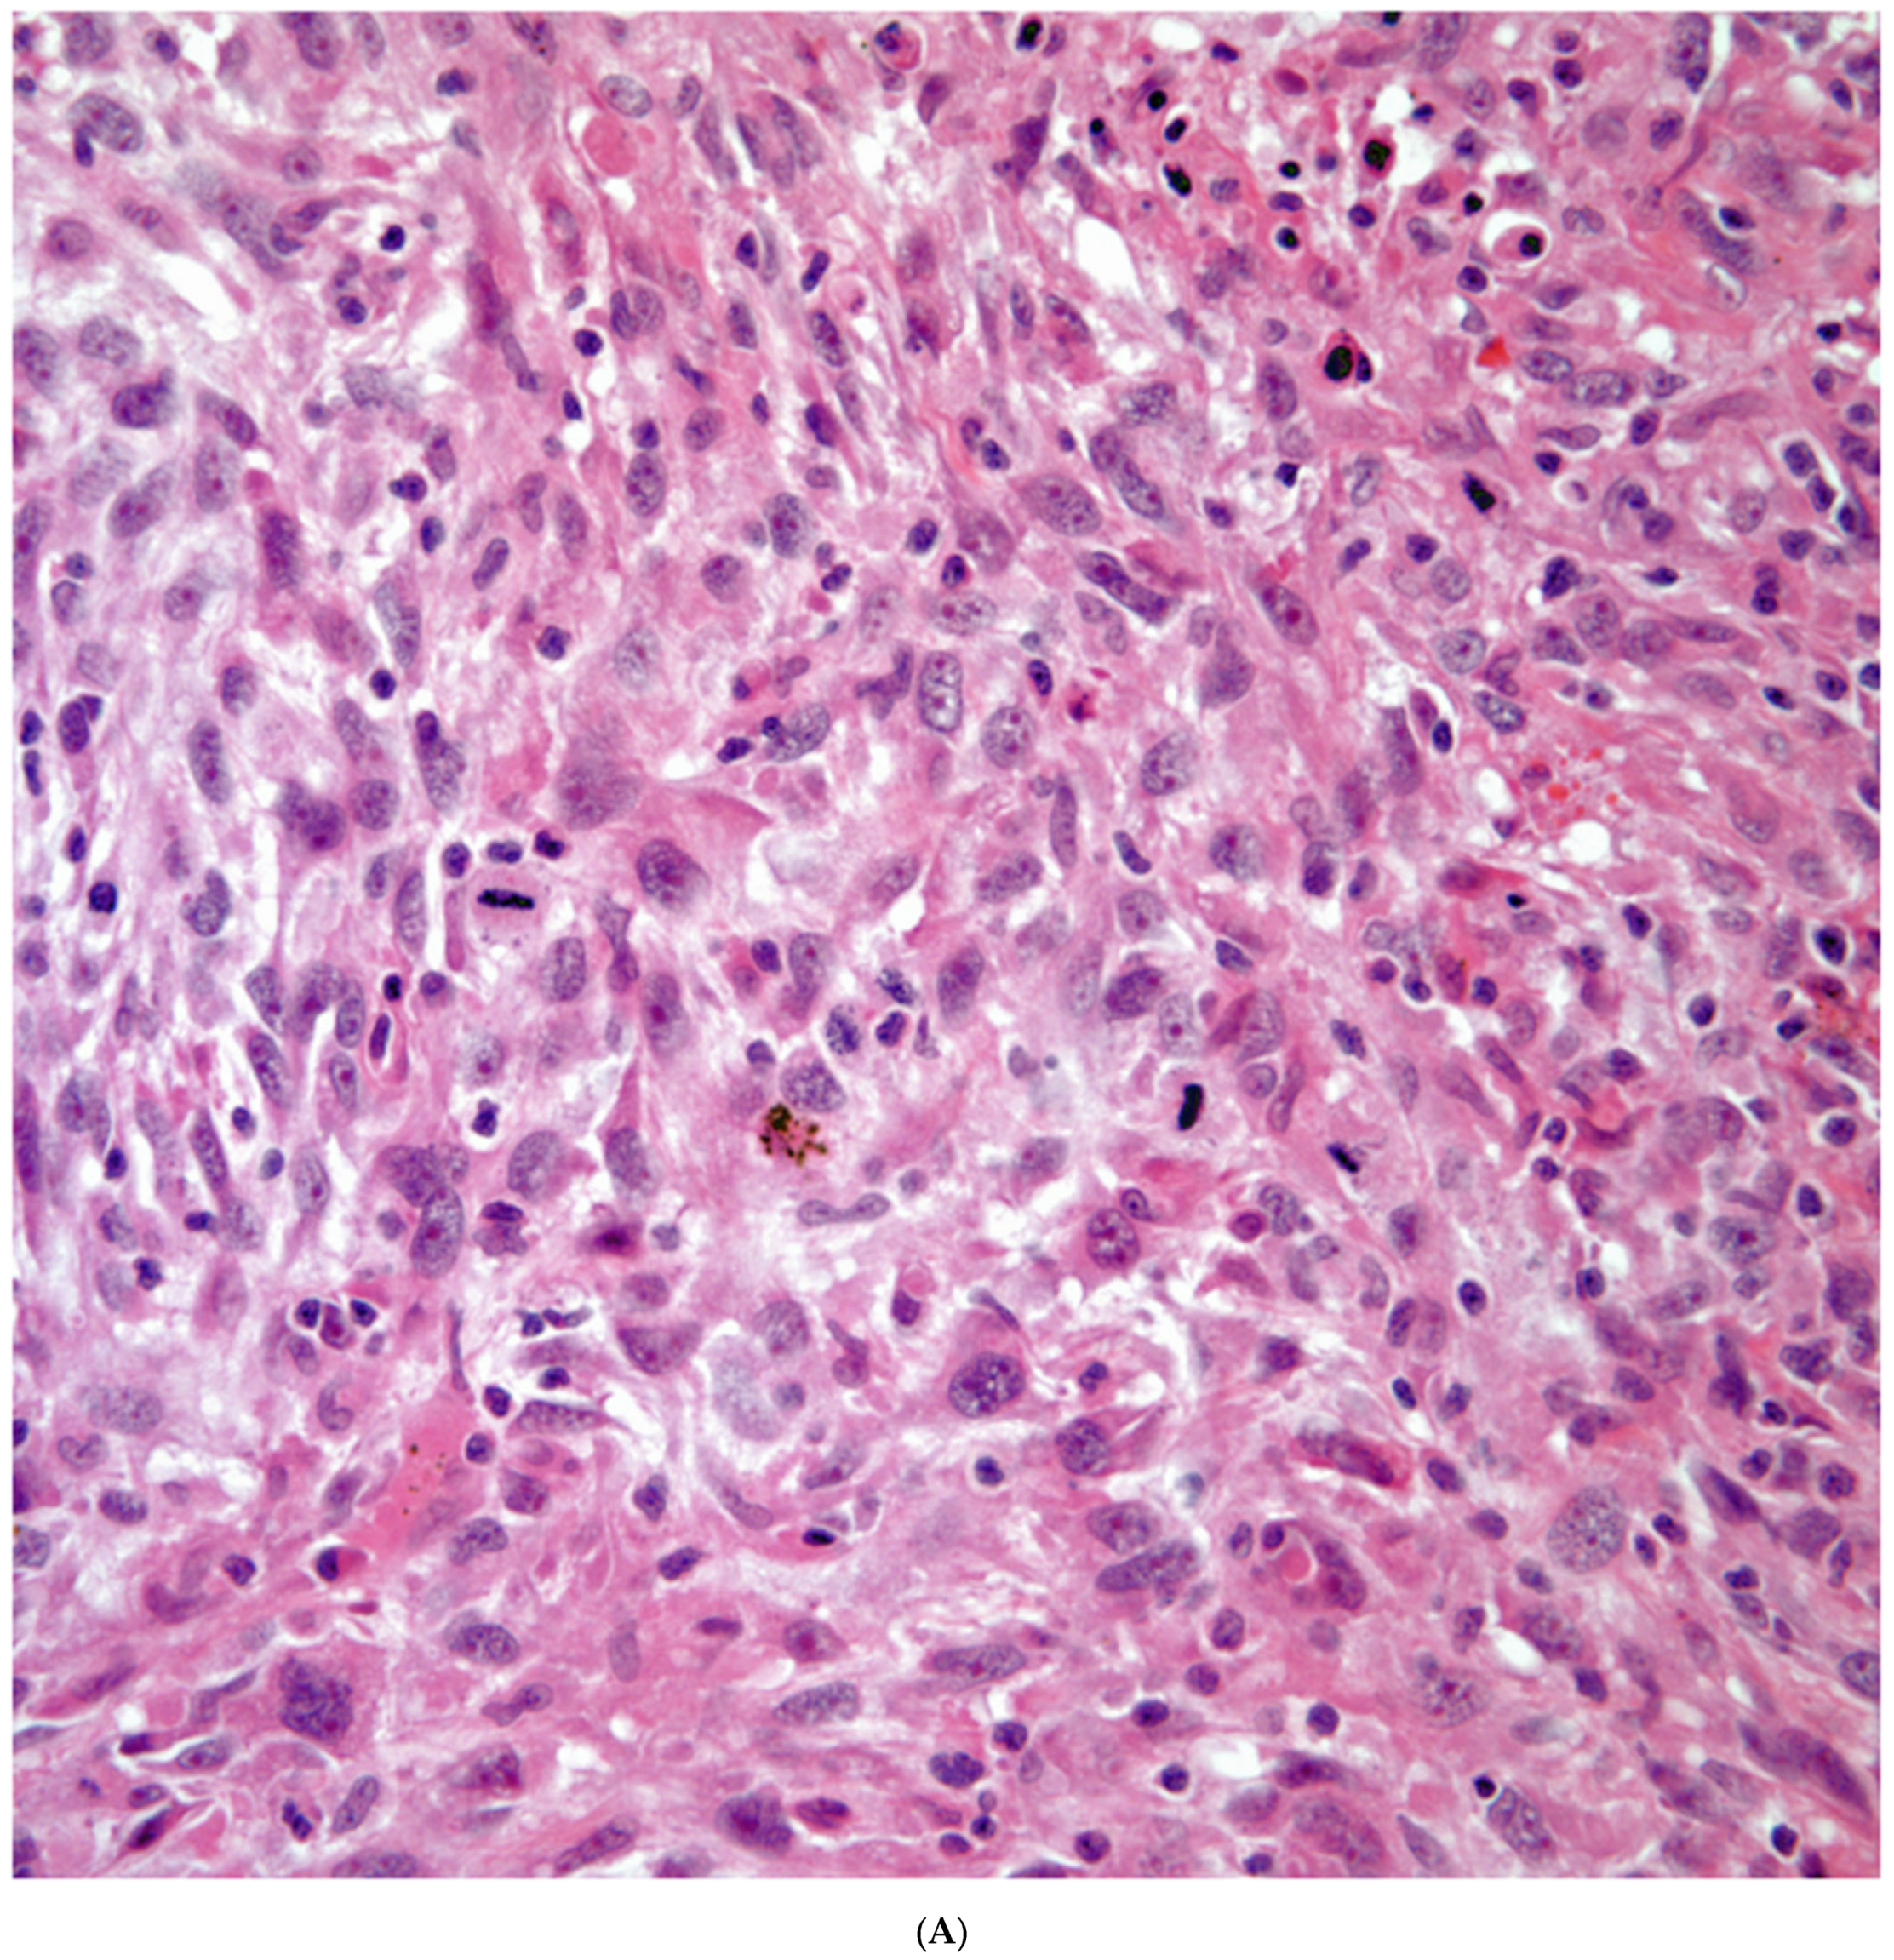

Sarcomatoid carcinomas: These tumors show a tightly packed spindle cell proliferation composed of slender cells with fusiform nuclei and inconspicuous nucleoli, replacing normal lung parenchyma. The tumors are well delimited but not encapsulated (Figure 1). Cellular atypia is variable and may show areas of mild to moderate to marked atypia. Mitotic figures also vary and may be inconspicuous or may be evident with the presence of atypical mitotic figures (Figure 2A,B). In high-grade tumors, the presence of necrosis and hemorrhage is prominent and is mixed with the neoplastic component. Important to recognize is that sarcomatoid carcinomas may be associated with areas of otherwise conventional non-small cell carcinoma such as adenocarcinoma or squamous cell carcinoma (Figure 3A,B). In addition, sarcomatoid carcinoma may also show the presence of bizarre giant cells admixed with the spindle cell component (pleomorphic carcinoma) (Figure 4).

Figure 2.

(A) Atypia and mitotic activity. (B) Neoplastic spindle cell proliferation.